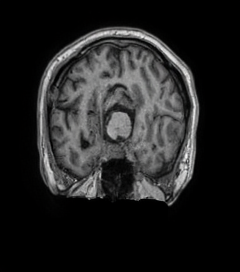

MRI